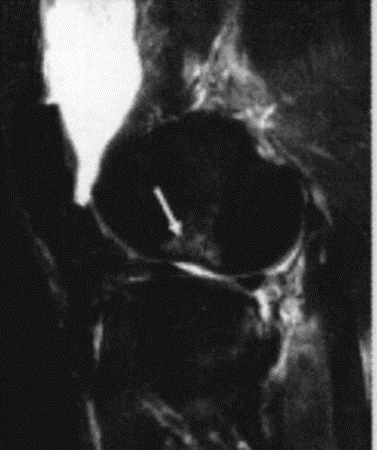

MRI可以提示前交叉韧带走形不连续、走形异常等异常信号,空髁间窝征、Notch征等可间接提示前交叉韧带损伤;

Notch 征: 股骨外侧髁凹陷加深加大或局部骨挫伤( 白箭头) , 提示 ACL 撕裂

空髁间窝征: 股骨外侧髁 ACL 止点空虚( 黑箭头) , 未见低信号影,附着于股骨髁, 提示 ACL 撕裂